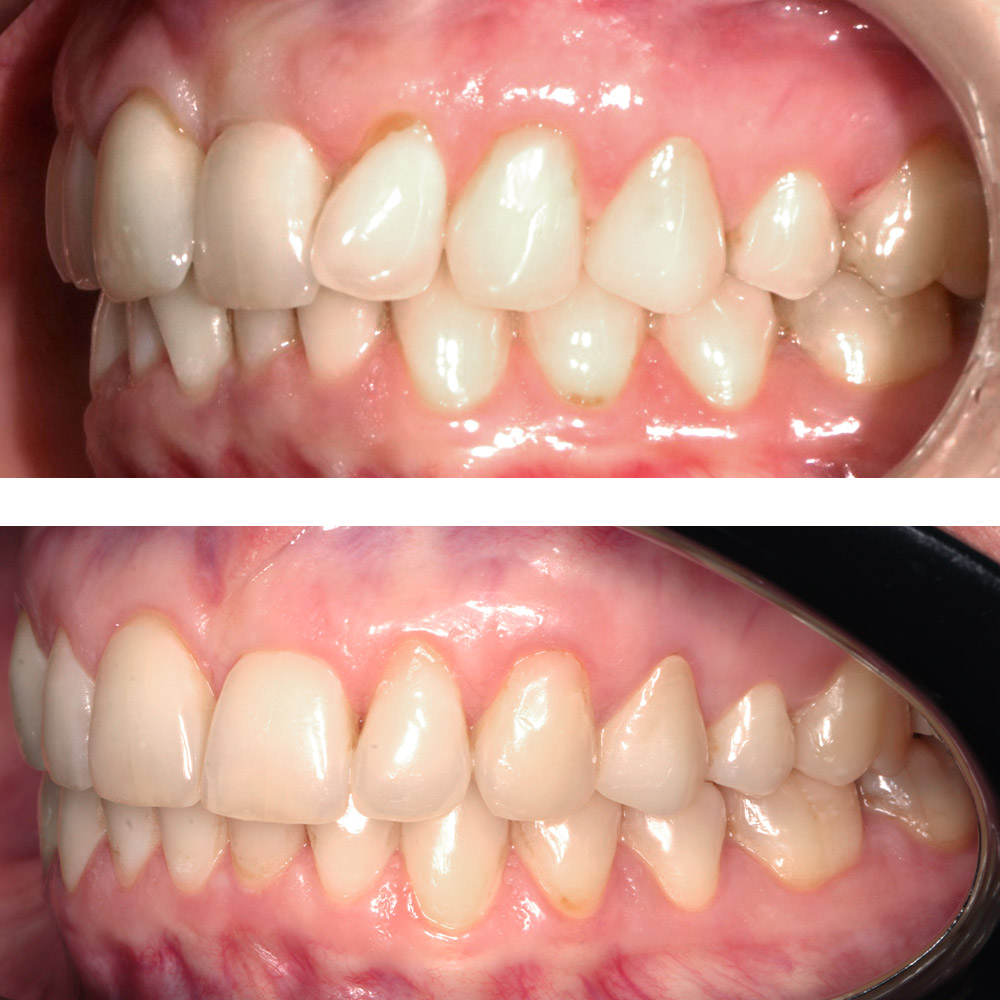

Кейс 21

Юрченко Павел Николаевич

Количество кап ВЧ 32

Количество кап НЧ 32

ДО

ПОСЛЕ